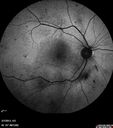

Prominent Posterior Hyaloid with Background Diabetic Retinopathy2401 viewsDiabetic patient comes in for follow up for her Background Diabetic Retinopathy and glaucoma. VA is 20/30. left eye. Fundus exam shows posterior Hyaloid with hemorrhage inferiorily.May 20, 2013

Prominent Posterior Hyaloid with Background Diabetic Retinopathy2710 viewsDiabetic patient comes in for follow up for her Background Diabetic Retinopathy and glaucoma. VA is 20/30. left eye. Fundus exam shows posterior Hyaloid with hemorrhage inferiorily.May 20, 2013